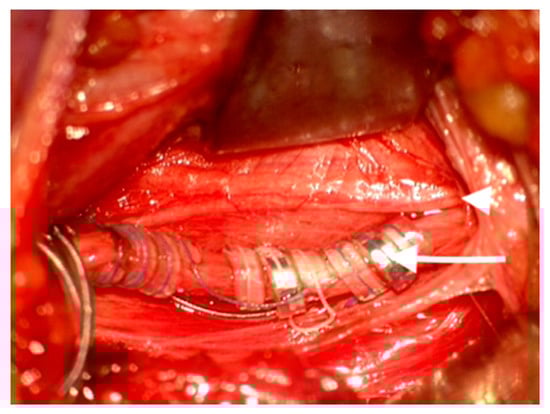

During dissection of the carotid sheath, a moderate-sized branch of the main vagus nerve trunk was identified postero-medially within the carotid sheath (Figure 1). Vessel loops were placed around the proximal and distal ends of the main vagal trunk and around the proximal portion of the medial branch. Intra-operative stimulation (0.3 mA monopolar stimulation) was delivered by a commercially available neurostimulator (Medtronic NIM® Eclipse, Minneapolis, MN, USA) to the vagus trunk and to the medial branch. The vocal cord responses were recorded by a commercially available EMG embedded endotracheal tube device used to detect vocal cord responses (Medtronic NIM® Flex, EMG Tube, Minneapolis, MN, USA). Stimulation of the common trunk and medial branch both elicited a compound muscle evoked potential from the left vocal cord. A similar latency period of 6 ms was detected following stimulation of both the trunk and the medial branch; however, the amplitude of the compound muscle potential was approximately half when the vagal trunk was stimulated as opposed to the medial branch stimulation.

Figure 1. Intra-operative images showing an aberrant branch (small white arrow) of the left vagus nerve (large white arrow) in the cervical sheath identified as a non-recurrent laryngeal nerve.